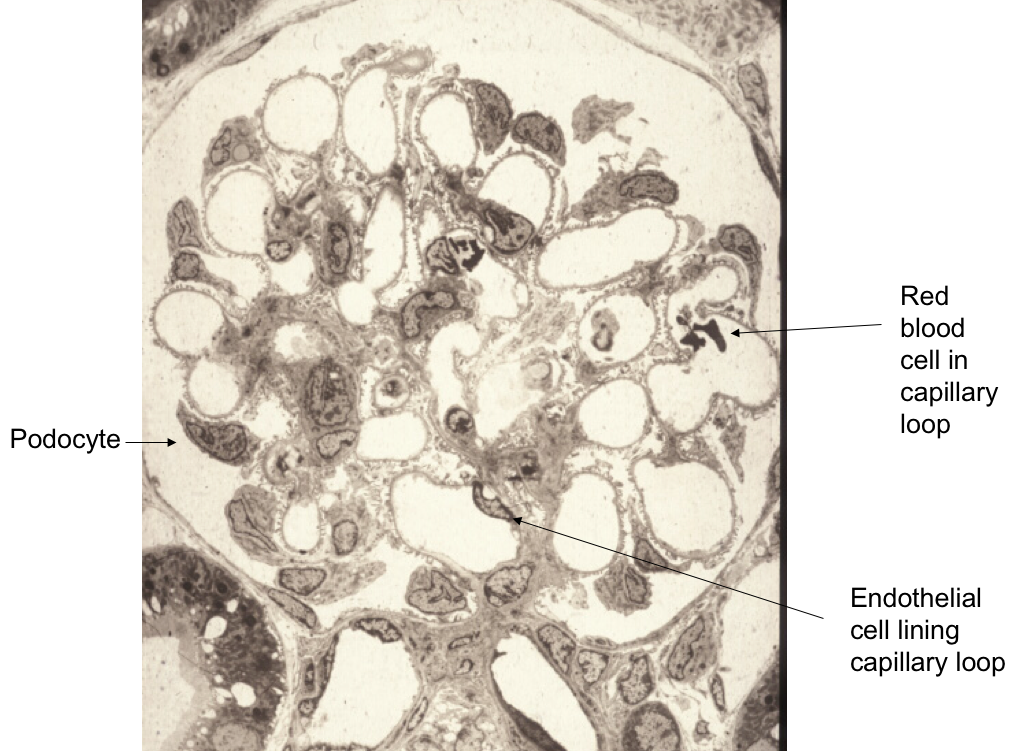

Podocytes are cells in the Bowman’s capsule in the kidneys that wrap around capillaries of the glomerulus

What structural feature do podocytes contain?

They have interdigitating ‘fingers’ or foot processes

What are the three layers of the filter barrier?

Endothelial cell

Basal lamina

Podocyte

What are mesangial cells?

Tree like group of cells which support capilalries